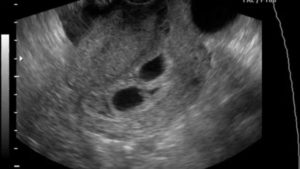

Беременность двойней определяется по прослушиванию двух сердечных ритмов, наличию двух полых оболочек с околоплодными водами (плодный пузырь), и двух эмбриональных органов (плацента или «детское место»). Хорион – источник развития плаценты и амнион – околоплодный пузырь, дают название типам развития близнецов в утробе.

Каждый эмбрион располагается в персональном околоплодном пузыре и имеет своё «детское место». При таком типе развития, близнецы, чаще всего, бывают разнояйцевые, и определить двойню на ультразвуковой диагностике возможно уже на пятой неделе вынашивания детей, то есть при первом проведенном женщине скрининге.

При данном типе беременности наличие двух детей можно заметить не ранее, чем на 9-11 неделе, поскольку дети находятся в разных амниотических пузырях, которые расположены в одном «детском месте».

Такую однояйцовую двойню УЗИ, как правило, не может показать на первом проведенном женщине скрининге. Эмбрионы соединены общей околоплодной оболочкой и расположены в одной плаценте. Дети данного типа вынашиваются тяжело, нередко с осложнениями.

Количество плодов определяется на первом ультразвуковом скрининге в 12-13 недель. Врач определяет: число плацент, наличие или отсутствие специальной перегородки, сердцебиение плодов. Двойня на УЗИ по фото выглядит как 2 эмбриона с обособленным или совместным амниотическим мешком.